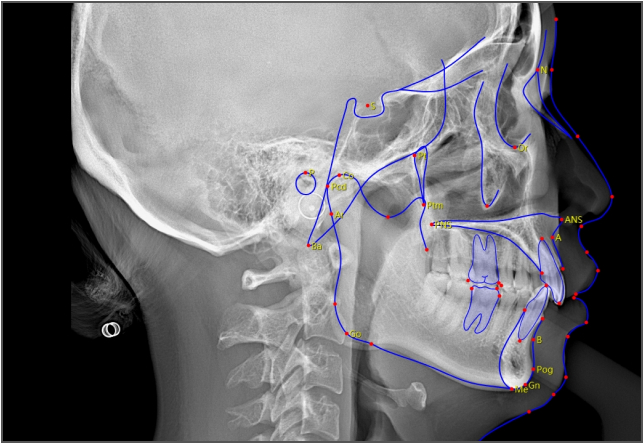

• lamtau AI頭影測(cè)量

AI頭影測(cè)量

單側(cè)頭影測(cè)量 專利 首創(chuàng)

偏頜患者的側(cè)位片左右側(cè)的影像不對(duì)稱,實(shí)際正畸測(cè)量時(shí)會(huì)產(chǎn)生較大的誤差。有方醫(yī)療推出單側(cè)頭影測(cè)量功能。這一功能有效解決了這一臨床問題,在口腔正畸領(lǐng)域廣受好評(píng),并于2023年成功獲得國家發(fā)明專利授權(quán)。

單側(cè)頭影測(cè)量